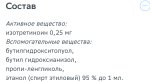

на днях проверенные люди посоветовали опробовать сироп пикрил (состав и описание на втором), говорят что очень хорошо помогает от акне при легких формах ( у меня такая), при этом без особого медикоментозного вреда для организма.

на днях проверенные люди посоветовали опробовать сироп пикрил (состав и описание на втором), говорят что очень хорошо помогает от акне при легких формах ( у меня такая), при этом без особого медикоментозного вреда для организма.

первый пик с сайта этого сиропа (понимаю что написать можно все что угодно)